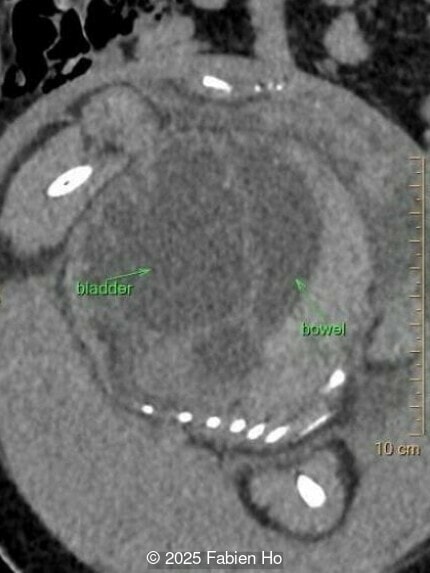

Our prenatal ultrasound revealed a male fetus with megabladder, dilation of both ureter and kidneys, and thinned kidney parenchyma consistent with Lower Urinary Tract Obstruction (LUTO). Additional findings suspected on ultrasound and confirmed on computed tomography included:

- Suspicion of dilated bowel in the left flank, in addition to dilated urinary tract

The findings of lower urinary tract obstruction, male phenotype, vertebral dysostosis, limb anomaly, and suspected bowel dilation led us to the following differential diagnosis:

- Prune-Belly syndrome

- VACTERL association

- MMHIS (megabladder microcolon hypoperistalsis), though usually described in females